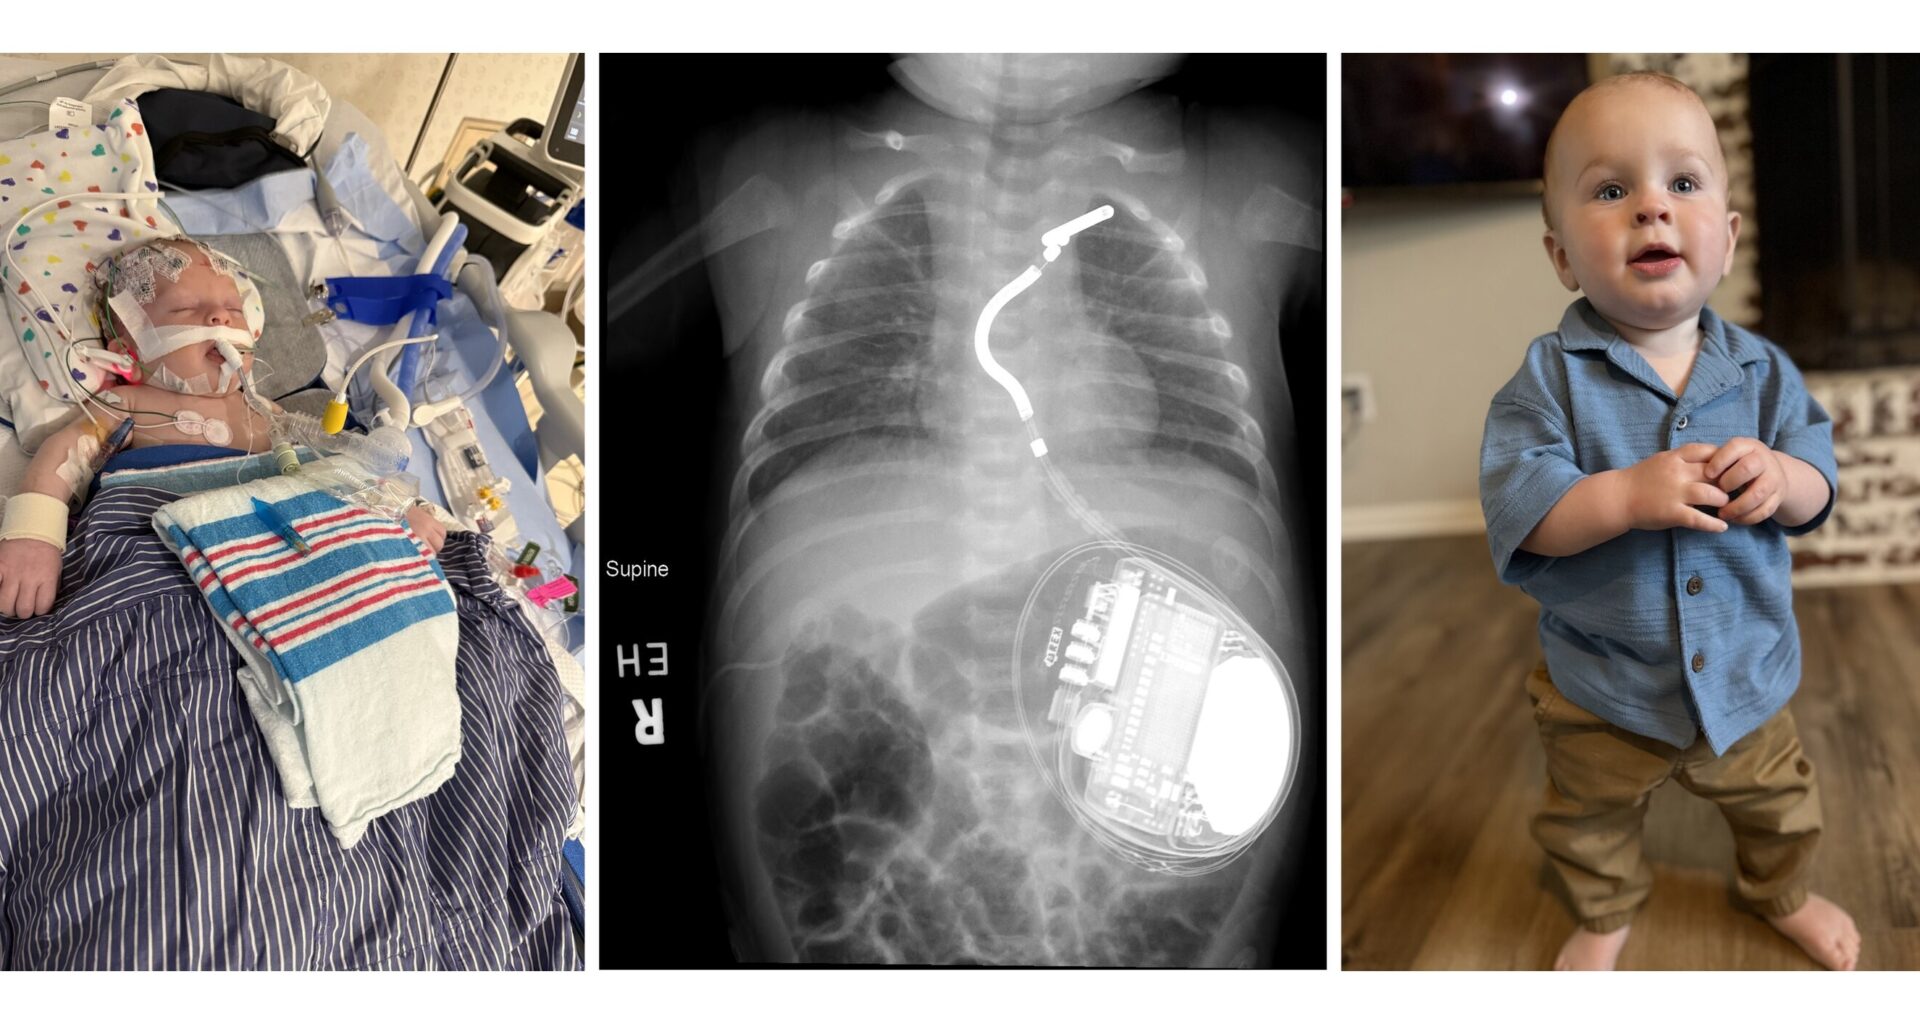

Meet Fletcher St. Jean, the youngest child to receive an EV-ICD device to manage idiopathic ventricular fibrillation

Fletcher St. Jean is the youngest child to receive an EV-ICD device to manage idiopathic ventricular fibrillation. A team at Cincinnati Children’s used a 3D virtual surgery planning tool to ensure the device could safely fit.

But even then, no one expected Fletcher would become the youngest and smallest child to ever receive an extravascular implantable cardioverter-defibrillator (EV-ICD)—a device needed to protect his heart from suddenly stopping.

While Fletcher remained under close watch in the hospital’s cardiac ICU, Sassan Hashemi, MD, another member of Division of Pediatric Cardiothoracic Surgery at Cincinnati Children’s performed a critical task. Using imaging data from Fletcher’s chest CT scan, Hashemi constructed a 3D model of Fletcher’s heart and chest cavity. The process took less than a day.

The 3D results mattered because if the surgical planning had considered only a flat 2D plane, there would not have been enough room to fit a critical 9-cm portion of the device’s lead. But by curving the wire in both vertical and horizontal ways there was just enough room, Connor says.

“This procedure would not have been possible without the 3D model,” Connor says. “It demonstrated that the lead could fit in the desired space and allowed for virtual trialing of multiple positions within the chest.”

The device and battery were placed in Fletcher’s abdomen below the rib cage, with the single, critical lead wire snaking vertically just below his breastbone to sit just in front of the heart but not directly attached to the heart tissue.